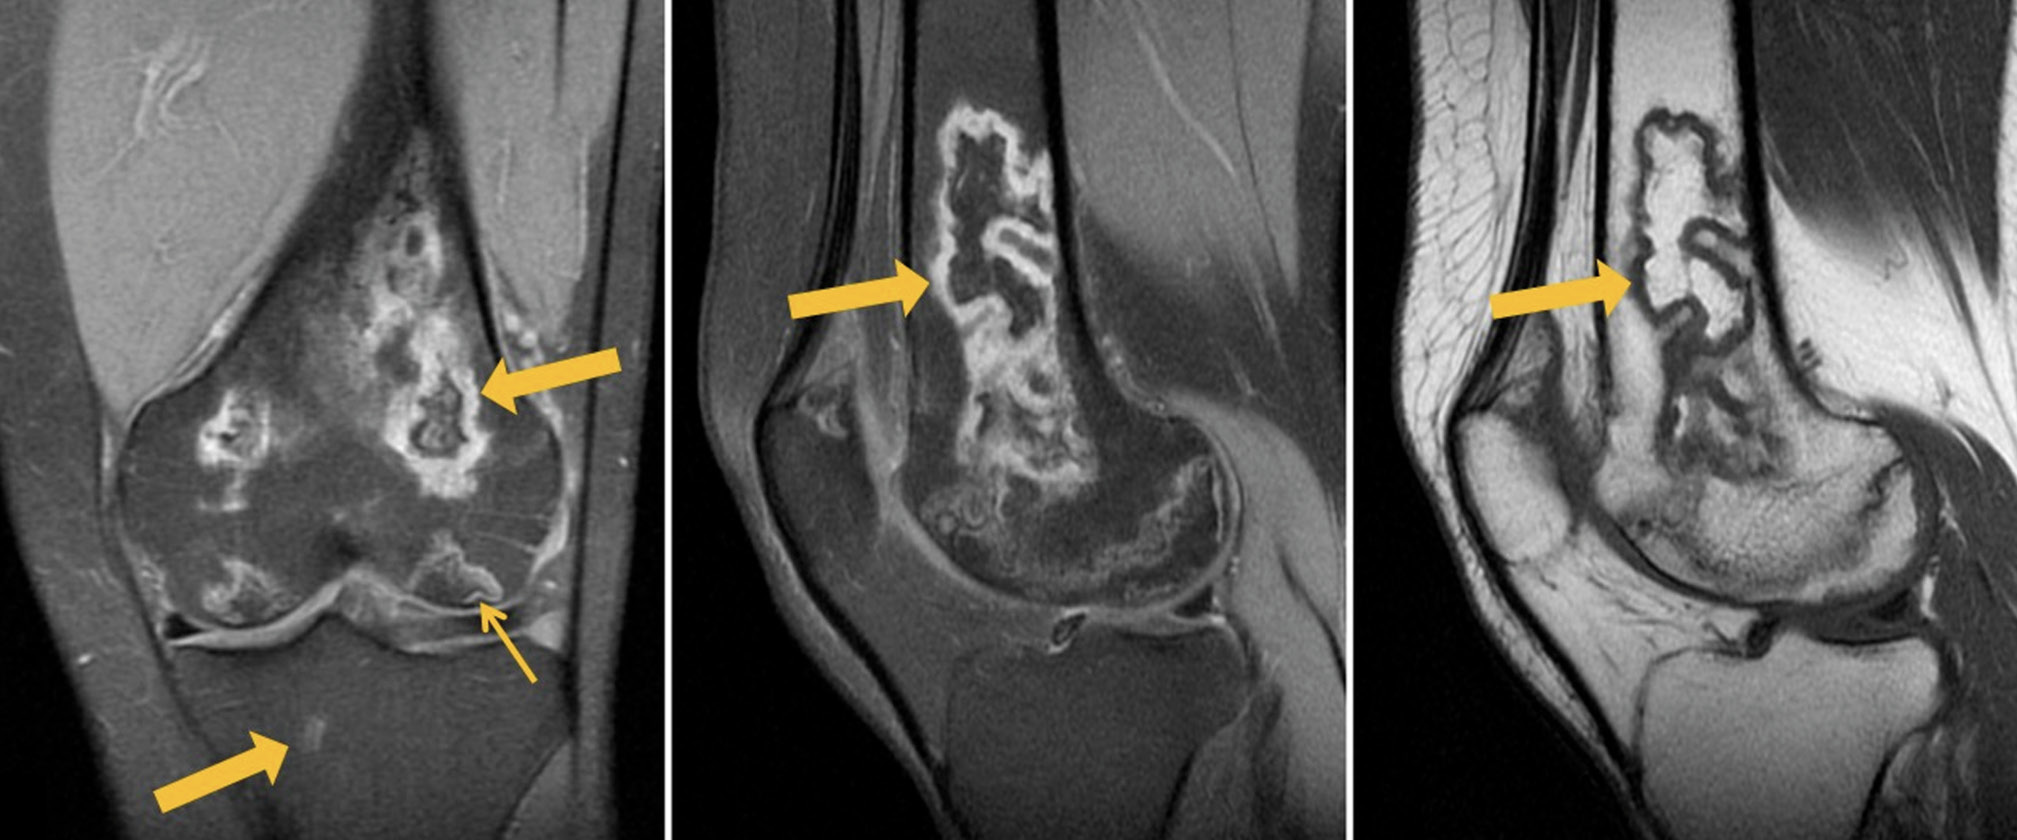

MRI of the left knee joint: lesions in the distal parts of the femoral diaphysis and femoral condyles (with involvement of the articular surface) as well as in the patella, inhomogeneously hyperintense on PD-weighted (proton-weighted) images with fat suppression and hypo-/isointense on T1-weighted images (T1WI), with an irregular (“geographic”) shape and yellow marrow signal areas visualized in the central parts (Fig. 1). MRI of the right knee joint: similar lesions of the bone marrow of both femoral condyles, with involvement of the distal metaepiphysis and articular surface of the lateral condyle as well as the patella. A perilesional “double line” sign is visualized over a short distance for some lesions (Fig. 2).

Fig. 1. Primary MRI of the left knee joint: PDWI with fat suppression in the coronal (а) and sagittal (b) plane and T1WI in the sagittal plane (с). The arrows indicate areas of bone marrow edema in the form of a heterogeneous, irregularly shaped (“geographic”) MRI signal of femoral and tibial condyles.